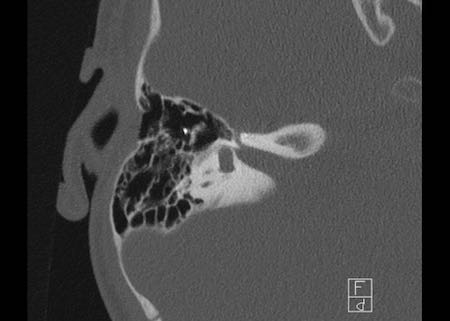

Bên trái là hình ảnh của một bé gái 2 tuổi.

Các hình ảnh từ kết quả chụp CT được thực hiện trước khi cấy ốc tai điện tử.

Quan sát thấy dị dạng nhẹ ở đỉnh ốc tai – không có sự phân tách giữa vòng thứ hai và vòng thứ ba, và trụ ốc tai xương vắng mặt.

Cống tiền đình bình thường.